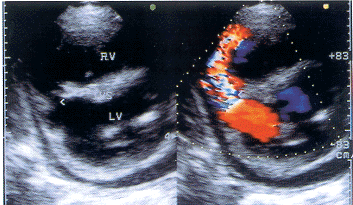

患者,男,74岁,胸闷气促20天,双下肢浮肿半月,加重5天,晕厥一次入院。查体:一般情况尚好,无紫绀,血压13.3/9.9Kpa,颈静脉充盈,两肺呼吸音增粗,右上肺可闻及哮鸣音,心率90次/分,律齐,心尖区及胸骨左缘三、四肋间可闻及Ⅳ/Ⅵ收缩期吹风样杂音,向腋下传导,心界向左向右扩大,心电图示急性下壁心肌梗塞,偶发室早。超声检查:主动脉根部内径33mm,左房内径49mm,左室内径收缩期35mm舒张期49mm,右室内径44mm,右房内径40mm,室间隔厚度10mm,左室后壁厚度9mm,左室下壁及后间隔从基底段至乳头肌水平回声减弱,变薄,呈反常运动,后间隔见一圆球样突向右室约3.5cm×2.9cm大小,并见中间约8mm回声失落,彩色血流显像见收缩期经缺口处自左室向右室五彩镶嵌过隔血流束(图1),并用连续多普勒将取样置于缺口右室侧,测得正向宽带湍流频谱,最高流速为3.8m/s,二尖瓣前后叶及主动脉无冠瓣回声增强钙化,用脉冲多普勒及彩色多普勒测得两瓣膜口轻度返流血流频谱,左室后壁心包腔内见收缩期23mm、舒张末期12mm液性暗区,应用连续多普勒经三尖瓣返流估测肺动脉收缩压68mmHg。超声诊断:1.急性左室下壁及后间隔心肌梗塞,后间隔室壁瘤并穿孔;2.心包中量积液;3.二尖瓣、主动脉瓣钙化伴轻度关闭不全;4.肺动脉高压(中度)。

图1 室间隔穿孔